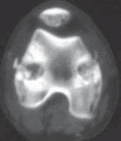

TECHNIQUES D E F GTECH FIG 2 •

(continued)

D. A photograph of a specimen demonstrating the ablation of the peripheral third of the physis, leaving the middle third of the physis intact. E. A photomicrograph of the femoral physis distally demonstrating the ablation of the peripheral third of the physis, leaving the middle third intact. F. A computed tomography section through the femoral physis distally demonstrates the ablation of the peripheral third of the physis. Note the narrow space in the middle third of the physis, with the neurovascular bundle posteriorly (between the femoral condyles) and the patellofemoral joint anteriorly. G. The 3-mm incision has been closed with a single suture. The incision is covered by an adhesive strip and bandage.Epiphysiodesis of the Fibula Proximally 1. The same incision is used to perform the epiphysiodesis of the fibula as the proximal physis of the tibia laterally.